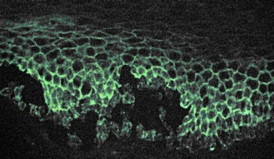

UB researchers have pinpointed important changes in cellular behavior that occur in Pemphigus Vulgaris, the rare, blistering skin disease shown in this microscopic image.